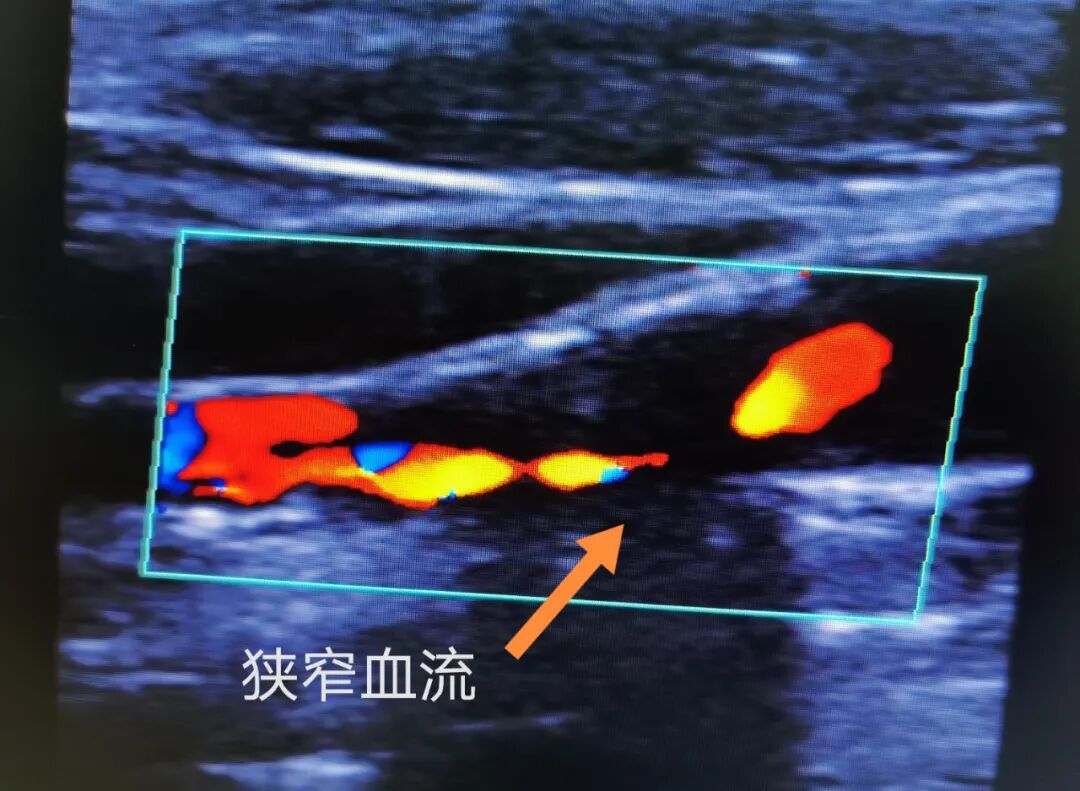

血管超聲圖片

陳阿姨“右側(cè)頸內(nèi)動脈起始部管腔狹窄約超出90%”,已屬于重度狹窄,血管內(nèi)僅有一絲血流經(jīng)過,急需盡快治療!經(jīng)過綜合評估,神經(jīng)醫(yī)學中心神經(jīng)外科血管介入學組為陳阿姨進行了“頸內(nèi)動脈支架植入術(shù)”。